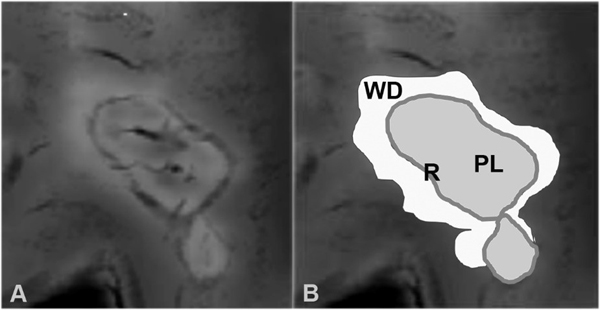

The possibility to detect accumulation of iron-loaded microglia in vivo by magnetic resonance imaging offers a very attractive tool to monitor the dynamics of active lesions and neurodegeneration in human disease. This is exemplified in multiple sclerosis, where the presence of an iron rim around the lesion identifies it as chronic active (Bagnato et al. 2011, Mehta et al. 2013, Hametner et al. 2013; Figure 3). Furthermore, such lesions show more pronounced tissue damage and neurodegeneration in comparison to those lacking an iron ring, and the presence of such lesions is associated with an aggressive clinical disease course (Absinta et al. 2016, Weber et al. 2021). Pathological data on the distribution of tissue degradation products in such iron lesions suggested that they expand very slowly, but the time course of their dynamic evolution was unknown. This has changed when prospective longitudinal MRI studies using iron sensitive sequences were performed, which provide data on dynamic changes in MS lesions over a time period of up to 7 years (Dal Bianco et al. 2017, 2021). Brain lesions without an iron rim shrank during the first 3 years and then their volume stabilized. In contrast, iron ring lesions slowly expanded over 3 to 5 years, before their size stabilized. These data indicate that chronic neurodegeneration in progressive multiple sclerosis is a very slow process, gradually developing over years, while demyelination and neurodegeneration in acute relapses develop within weeks.

Figure 3: Slowly expanding iron ring lesions in the MS brain can be visualized on MRI with iron sensitive imaging sequences. The typical presentation of such lesions reveals high iron signal in one or several central veins and in a rim at the lesion edge, reflecting iron-containing activated microglia. The iron rim (R) demarcates the demyelinated plaque (PL); the abnormal MRI signal around the iron rim is due to Wallerian Degeneration (WD).

Direct neuropathological analysis of MRI scanned tissue blocks showed that the iron ring seen in MRI always reflects the iron-loaded microglia at the edge of active plaques, while the T2 signal of the lesions gradually expands outside the ring (Dal Bianco et al. 2017, 2021). These lesion changes reflect an expanding halo of secondary Wallerian degeneration around a destructive lesion (Figure 3). Thus, the quantitative lesion load, determined on MRI, not necessarily indicated lesion load, but also Wallerian degeneration in the normal appearing white matter.